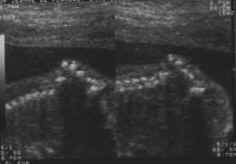

Coupes sagittales : parcourant tout le rachis (cliché gauche).

Coupes transversales : vertèbre par vertèbre (cliché droit).

- Sur une coupe sagittale stricte : corps vertébraux, canal rachidien (deux fines lignes parallèles) suivi jusqu’au cône terminal (effilé) et intégrité du revêtement cutané.

- Sur une coupe para-sagittale : corps vertébraux et lames latérales.

de dedans en dehors, corps vertébraux, canal rachidien, lames latérales, revêtement cutané.

Coupes frontales : Deux lignes parallèles discontinues régulièrement, correspondant aux lames latérales, au milieu le canal rachidien.

Existence d’un renflement lombaire précédent l’effilement terminal sacré.